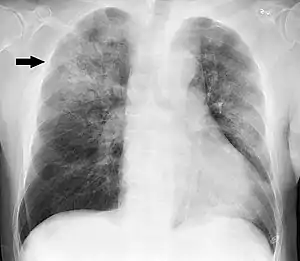

Clinical features may include initial symptoms of an upper respiratory tract infection mimicking a viral infection, usually associated with low-grade fevers. This may progress to the lower respiratory tract within a few days, with features often resembling those of wheezy bronchitis. Sputum may be difficult to expectorate and is often grey or creamy in color. The cough may persist for weeks without appropriate treatment. Many cases are diagnosed after presenting chest infections that do not respond to penicillins or first-generation cephalosporins. A chest X-ray can identify alveolar consolidation.[27]